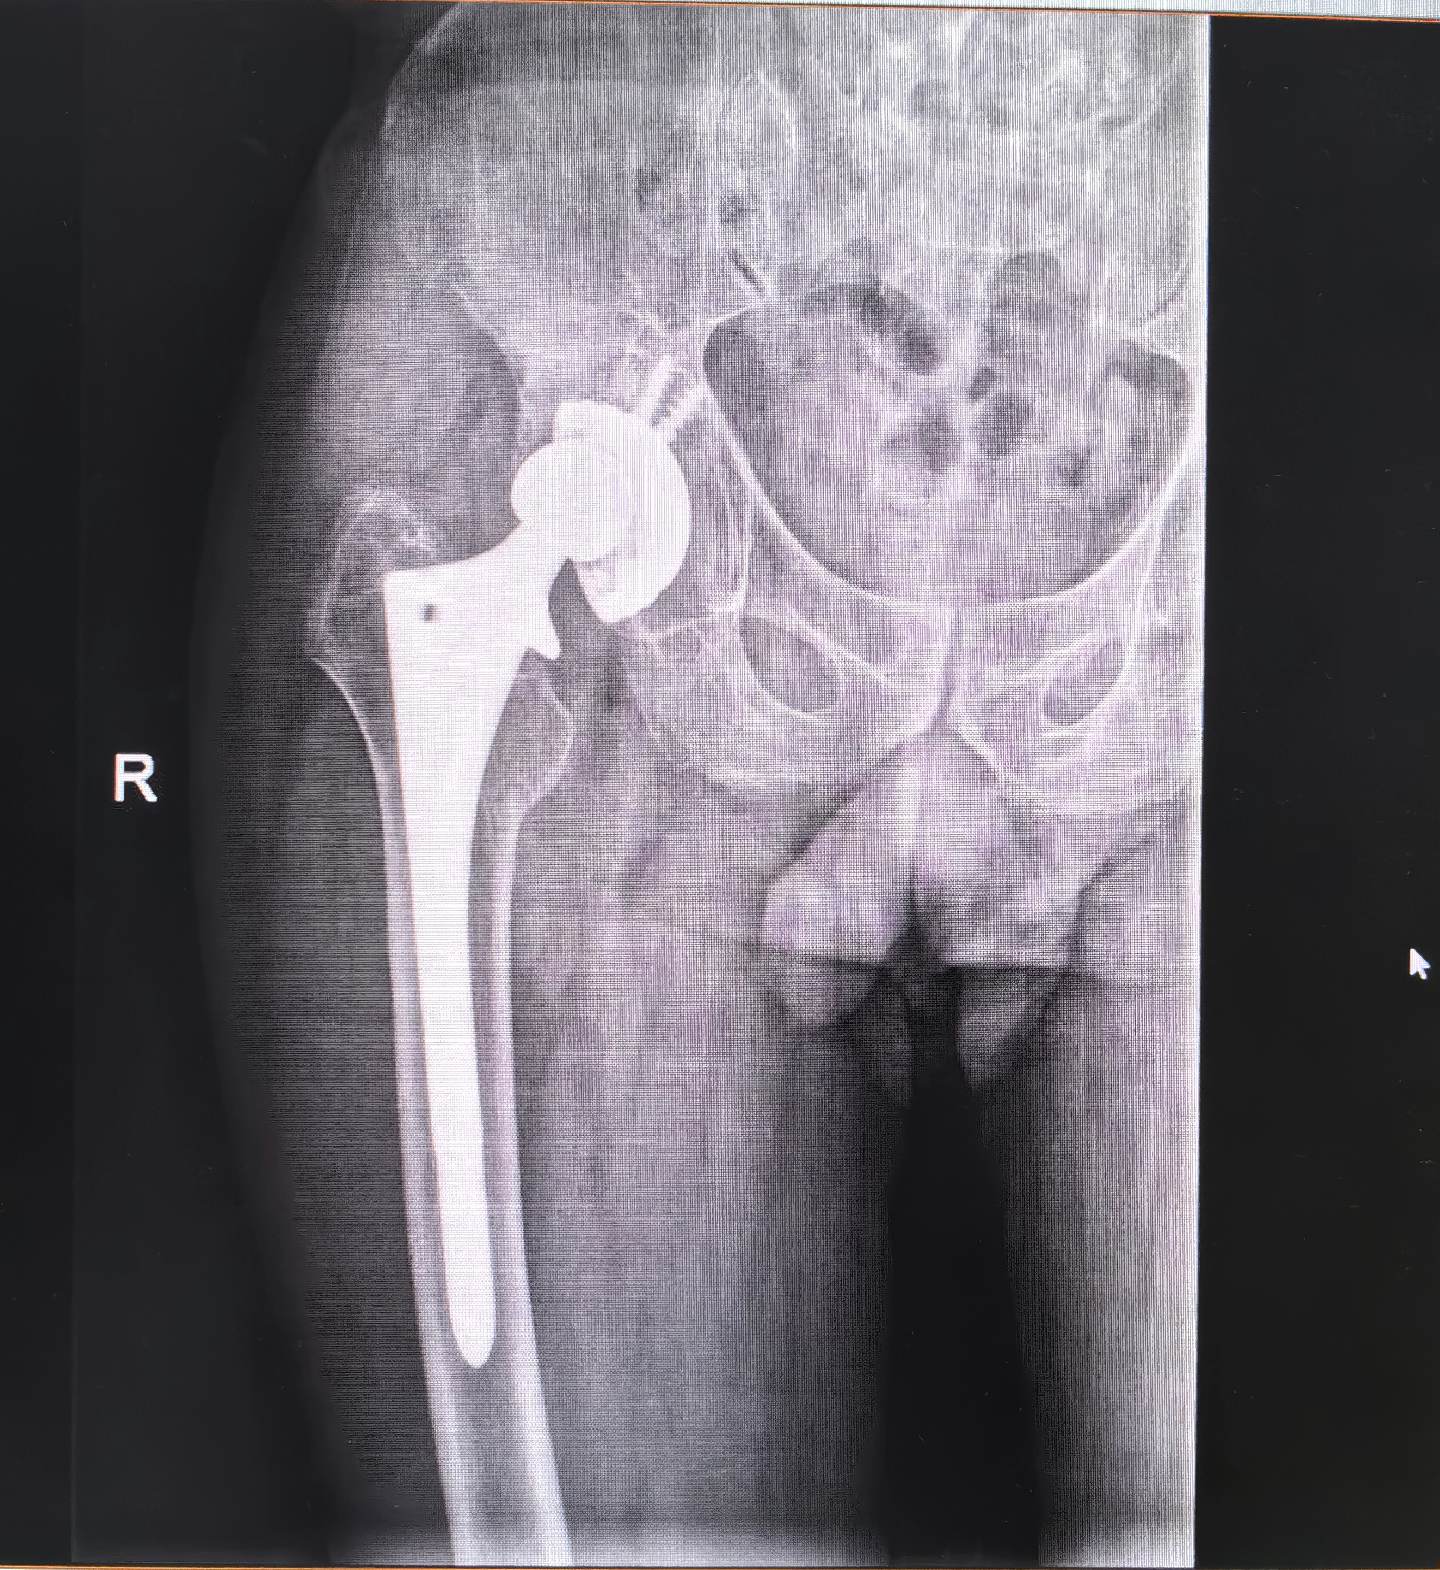

髋关节置换术后假体松动。髋关节置换术后假体松动,一定要做髋关节ct,此例髋臼内壁缺损明显,好在髋臼环完整,缺损处植骨,髋臼初始稳定性良好,术后两天正常下床,患者满意度很高🌹